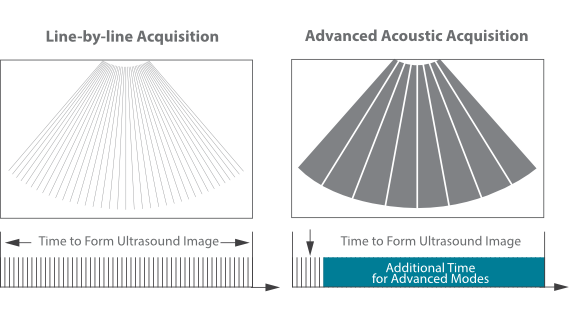

Akuisisi Akustik Canggih

Pemfokusan Piksel Dinamis